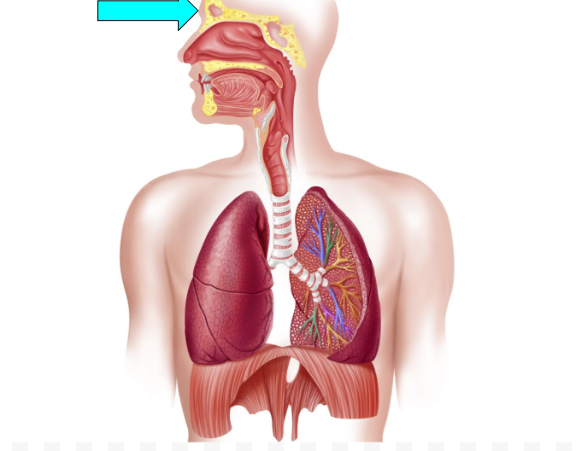

Frontal Sinus (pic)

Sphenoidal Sinus

helps to humidify & warm air, trap & flushes out germs